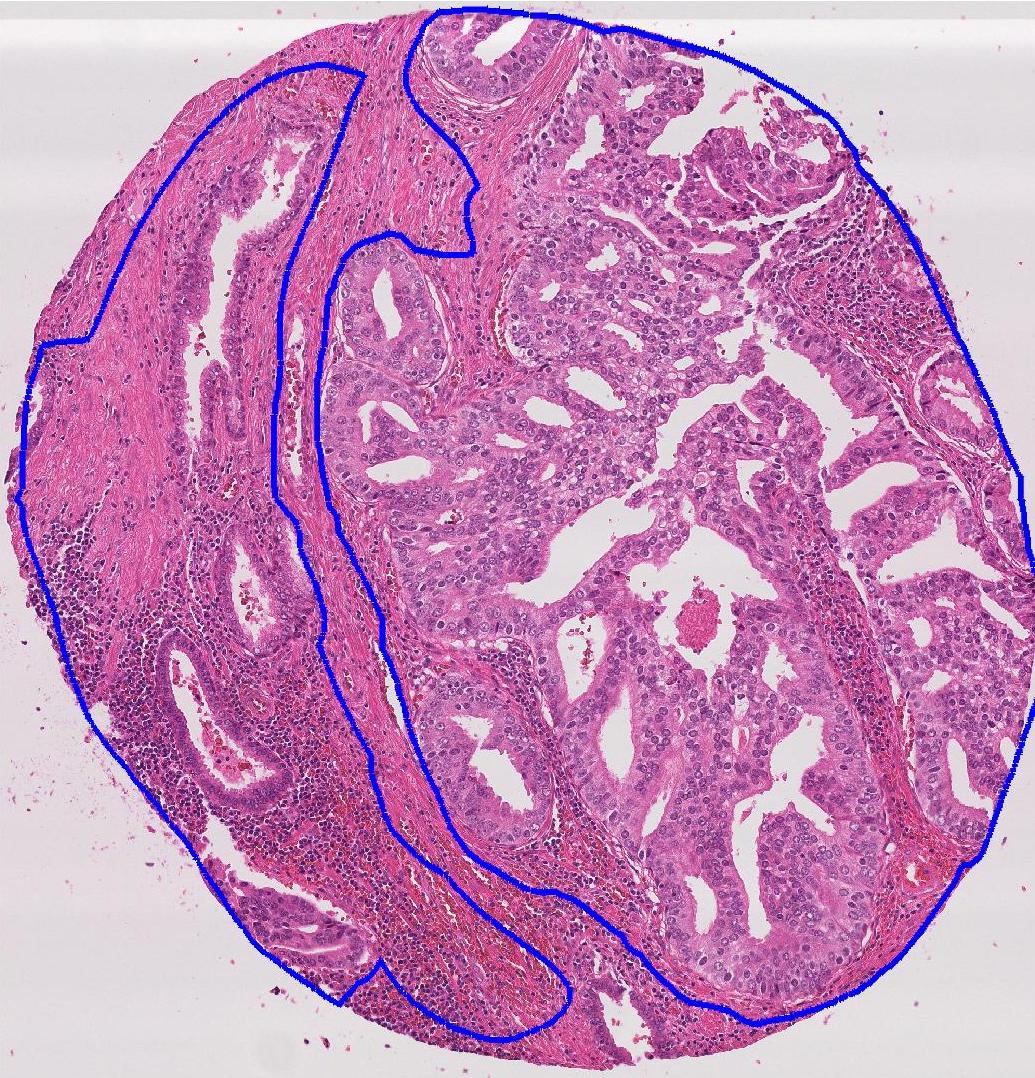

Ground truth maps obtained from the semi-supervised learning step has labels for each block. Consequently, there will be cases where a pixel outside the actual structure of interest shares its label since it is part of the block. This erroneous labeling is referred as label noise. Our experimental results show that the UNet++ network is more robust to such label noise than the conventional UNet. Figure 4 shows comparative results of using UNet and UNet++ in obtaining the weak segmentation map. UNet++ proves to be more robust to initial label noise. Figure 5 shows example images, their corresponding expert annotated manual segmentation maps, and the maps obtained using our method. A very high degree of agreement exists between weak supervision generated maps and the ground truth, with a Dice Metric of validating this observation. Without the label refinement step we obtain a Dice Metric of , highlighting its contribution in improving segmentation performance. Using UNet we obtain a Dice metric of and (without label refinement), which indicates superior capacity of UNet++ to overcome label noise. Thus we repose high confidence in the weakly supervised generated label maps as representing the correct labels and are reliable enough to model inter-label geometric relationship (as described in the next step).

![]() |

| (a) | (b) | (c) | (d) |

| (a) | (b) | (c) |